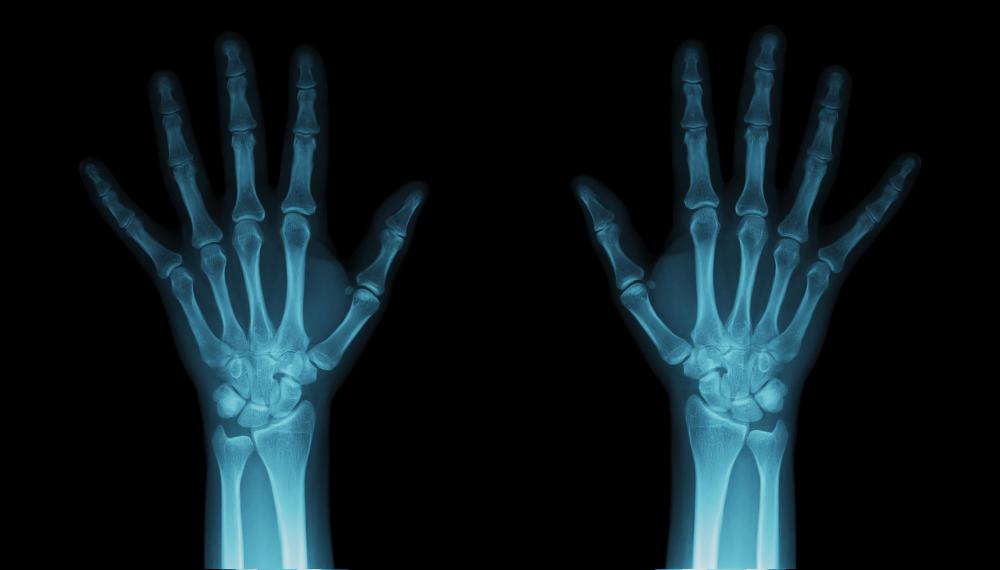

Hairline Fracture Symptoms Finger . If you fracture your finger, pain is likely the first symptom you’ll notice. Pain develops gradually in patients. what are the symptoms of a broken finger? What to do if you have a hairline fracture. The sooner a fracture is addressed by a doctor, the better the. this mnt knowledge center article discusses the risk factors, causes, and symptoms of a hairline fracture, as well as how to treat one. signs and symptoms of a broken finger include: If you suspect you have a. symptoms of hairline fractures. other symptoms can include visible bruising, swelling, and tenderness when you touch the area. if you suspect you have a finger fracture, seek treatment as soon as possible. fractures of the finger usually present with localised swelling, bruising, tenderness, with or without deformity. Pain when touching the bone.

fractures of the finger usually present with localised swelling, bruising, tenderness, with or without deformity. if you suspect you have a finger fracture, seek treatment as soon as possible. what are the symptoms of a broken finger? symptoms of hairline fractures. Pain develops gradually in patients. If you suspect you have a. If you fracture your finger, pain is likely the first symptom you’ll notice. this mnt knowledge center article discusses the risk factors, causes, and symptoms of a hairline fracture, as well as how to treat one. signs and symptoms of a broken finger include: Pain when touching the bone.